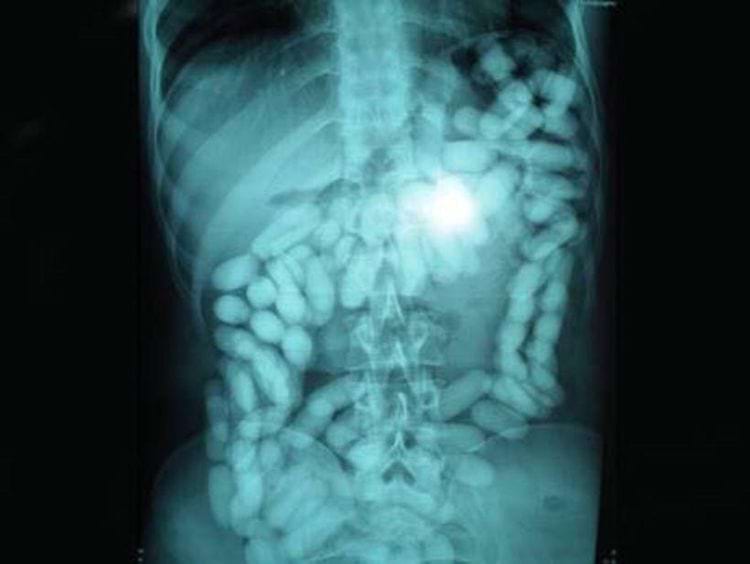

Вот как выглядит на рентгеновском снимке, когда вы сдерживаете газы (воздушный карман между костями таза)